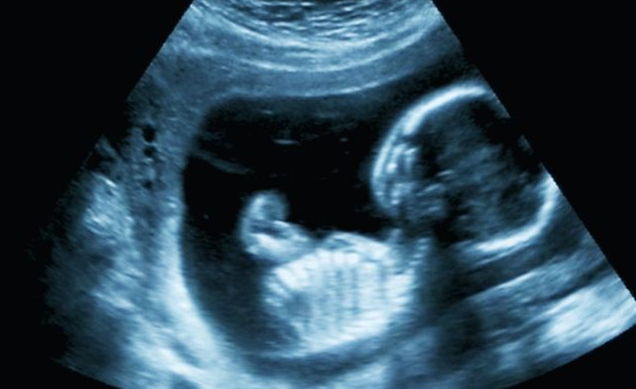

يتم معرفة جنس الجنين بعد فترة قليلة جدًا من الحمل، وذلك بعد عدد مرات من المتابعة مع الطبيب وإجراء السونار، وذلك يكون في بداية الشهر الرابع ويكون مع حلول الأسبوع الـ 18 من بداية الحمل.

فمن الصعب أن يتم تحديد نوع الجنين مع استخدام جهاز الموجات فوق الصوتية، وذلك في حال كان الجنين بالوضعية التي تسمح بالكشف عن الأعضاء التناسلية ومعرفة نوعه.

يظن البعض أن رؤية الولد في السونار تكون أسرع من رؤية الفتاة، وذلك من الأمور التي نوه عنها بعض الأطباء، والتي تم فيها الحديث عن تحديد جنس المولود وفي أي أسبوع يمكن معرفته، وقد تبين من خلال التوضيحات أنه يمكن معرفة جنس المولود الذكر في الأسبوع الـ 13 من الحمل وهذا على عكس الأسبوع التي يتم من خلاله رؤية جنس المولود بشكل عام والذي يكون في الأسبوع الثامن عشر.